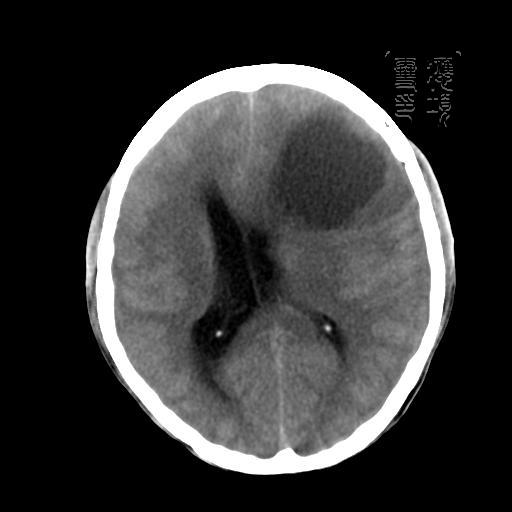

m 52y

二月前癫痫入院, 无既往史,现头痛、呕吐、视力减退、复视行ct平扫及增强检查。

左额叶囊实性占位,以囊性为主,并见明显强化不规则壁结节,占位效应明显,首先考虑是囊性星形细胞瘤.

考虑:囊性星形细胞瘤可能性大 。

考虑囊性星型细胞瘤可能性大。

谢谢楼上的朋友们!

结果已经在最后一幅图片内,感兴趣的,另存此图用记事本打开,往下拉就可看到。